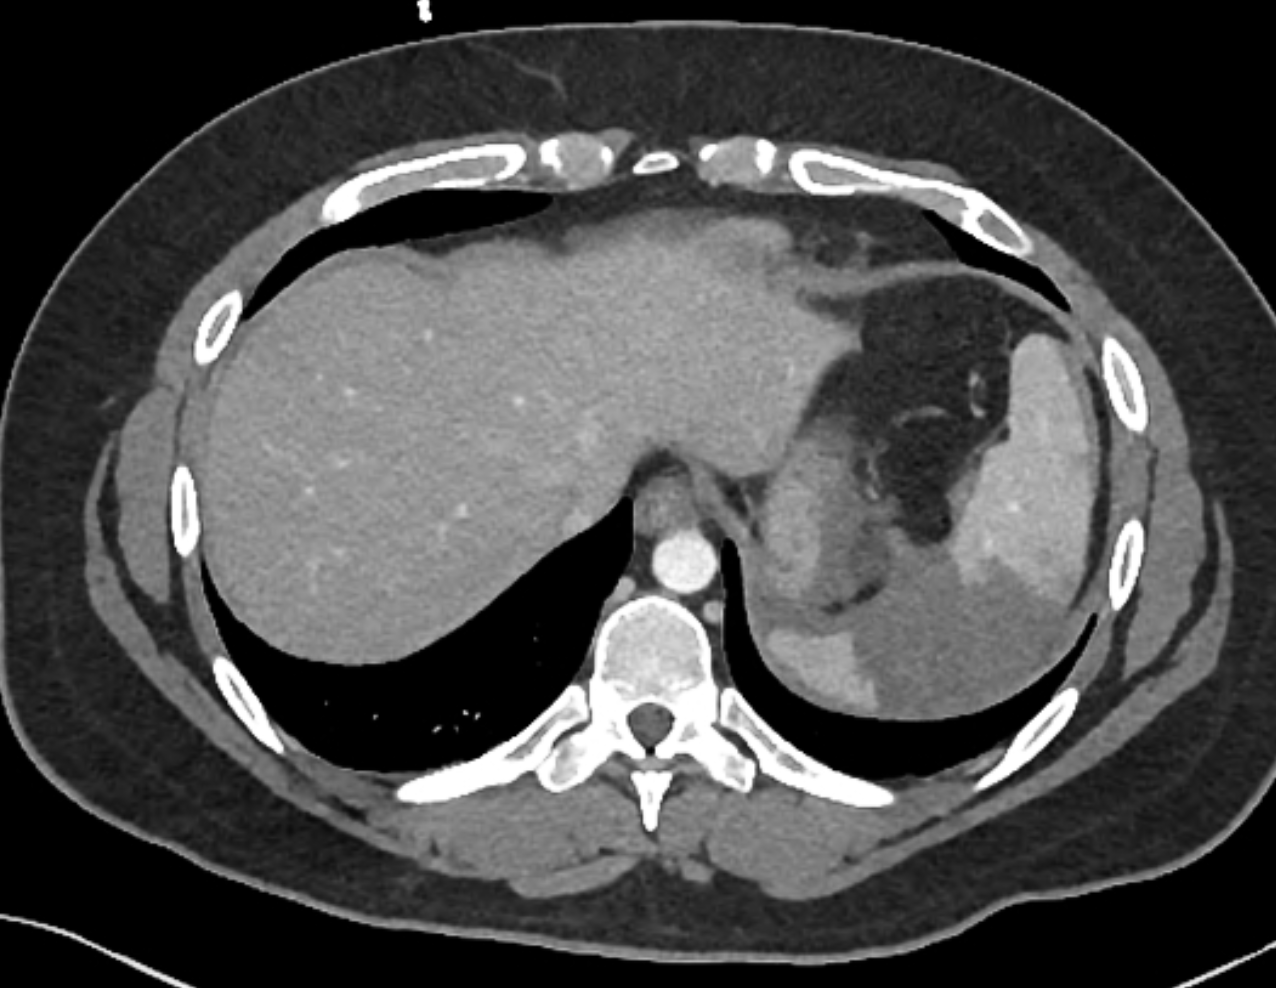

Moderate volume of free intraperitoneal fluid, particularly around the spleen which has a small hypodense and superficial cleft posteriorly, suspicious for grade I laceration.

Patchy fat stranding and fluid is seen within the small bowel mesentery, in the region of mesenteric vessels. Small foci of higher density are seen within the fat stranding, immediately adjacent to vessels and suspicious for venous bleeding. The bowel loops themselves show no gross abnormality and there is no free gas.

Lap belt subcutaneous bruising overlies the epicentre of the mesenteric abnormality.

Case Discussion

Injuries demonstrated in this case:

mesenteric tear with (probable) active venous bleeding

grade 1 splenic laceration